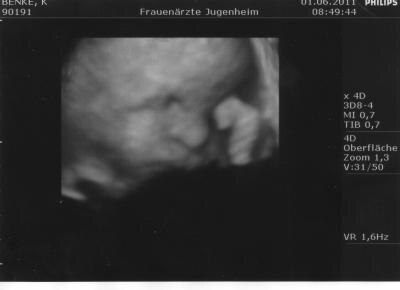

Hallo! Sorry, daß ich mich lange nicht mehr gemeldet habe. Ich mußte letzt Wochew mit Verdacht auf Gestoase ins Krankenhaus. Gott sei Dank hat sich nichts Schlimmes ergeben. Schweangerschaftsdiabetis hat auch nichts ergeben.Bekomme halt von Natur aus große, schwere Kinder. Sonst war heute alles gut und endlich habe ich auch mein 4 D Ultraschall bekommen. Eines hat er mir mitgegeben die anderen folgen dann per Mail. Ich hoffe Euch geht es allen gut. Liebe Grüße Kathrin

dann ist ja schön das bei euch alles gut ist.. und es ist ein sehr süsses bild.. liebe grüße

Oje, na du machst ja Sachen! Na gottseidank ist soweit alles im grünen Bereich! Freut mich für dich! Und das Foto ist ja auch wirklich goldig! GLG